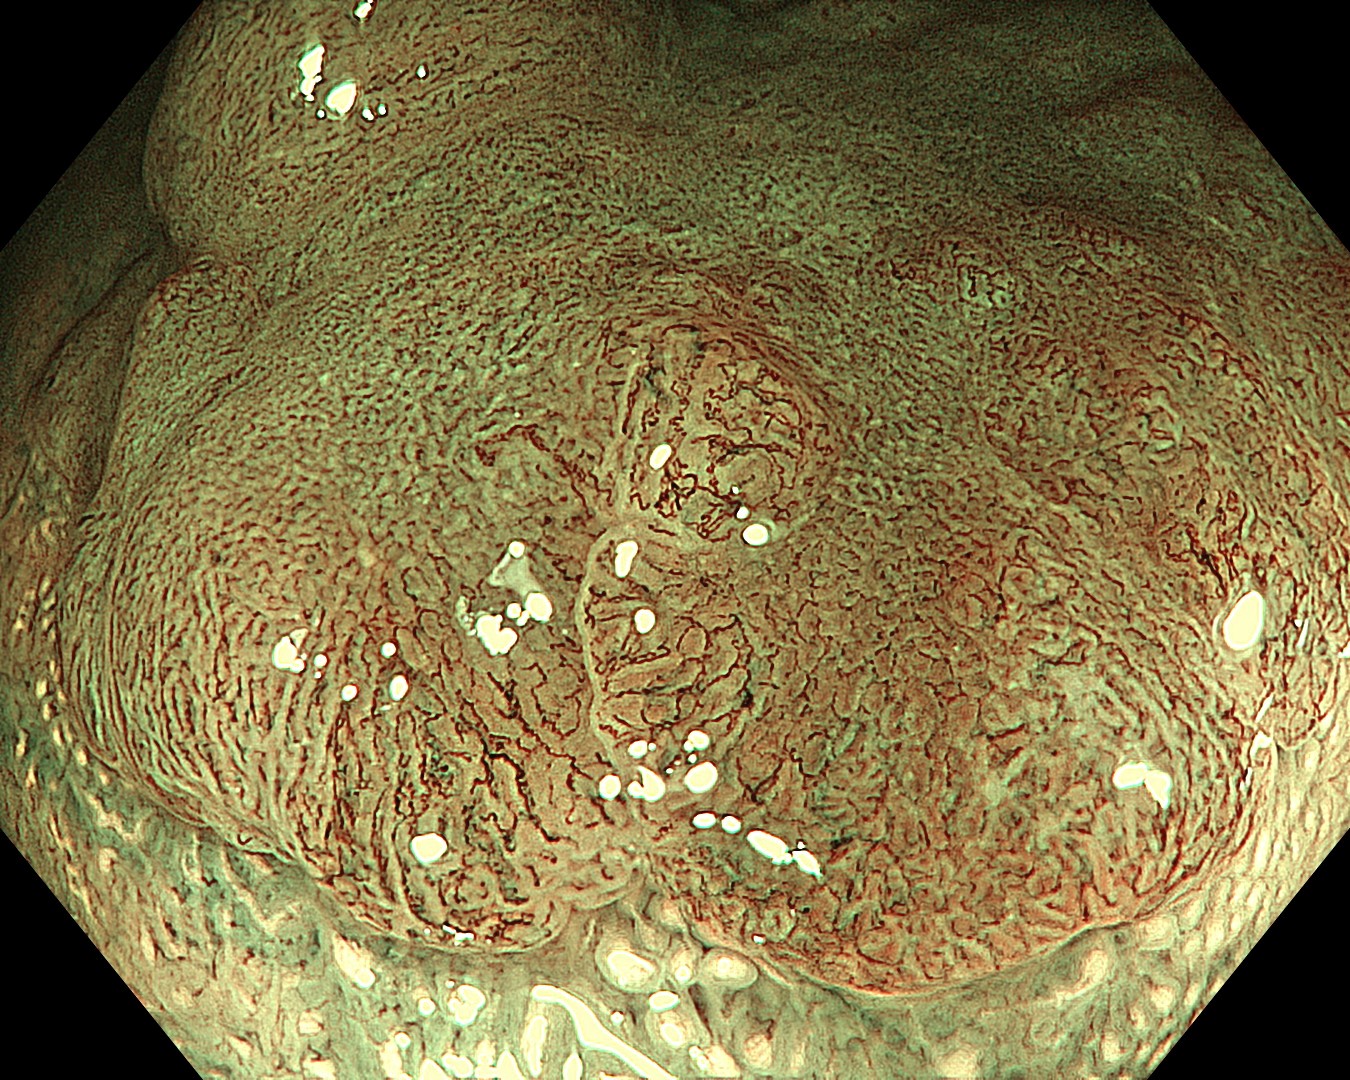

• NBI観察③(拡大)

強調設定:B8

図5

関心領域周囲では、表面構造・血管走行ともに不整で、Vessel Pattern・Surface PatternともにJNET type 2Bの所見であった。一方、関心領域では、表面構造・血管走行ともに不明瞭であり、JNET type 3も否定できない所見であった。

• NBI+TXI観察①(拡大)

切替前:NBI強調設定:B8

NBI+TXIレベル:高

図6

NBI+TXI観察では、従来のNBIに比べ、表面構造・血管走行ともに強調される。不明瞭な関心領域内に、分岐の異常な表面構造や分布の不均一な血管走行が確認され、JNET type 2B と診断しえた。